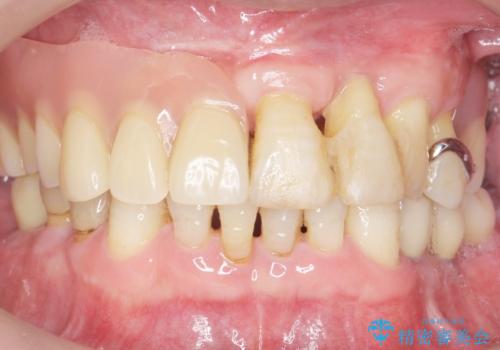

- 奥歯の違和感を主訴に来院された患者様です。

精査したところ、右下の奥歯は大きなう蝕により保存不可能な状態でした。

患者様のご希望により、抜歯後インプラント治療を行いました。

奥歯でしっかりと咬むことができるようになり、大変喜んで頂けました。